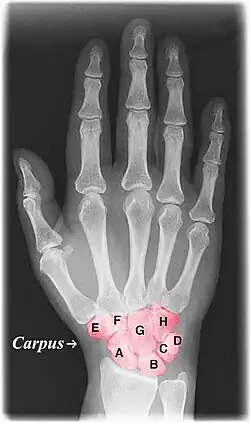

![]() Labelled image showing the eight carpal bones. | |

The carpal bones are the eight small bones that make up the wrist (carpus) that connects the hand to the forearm. The term "carpus" and "carpal" is derived from the Latin carpus and the Greek καρπός (karpós), meaning "wrist". In human anatomy, the main role of the carpal bones is to articulate with the radial and ulnar heads to form a highly mobile condyloid joint (i.e. wrist joint),[1] to provide attachments for thenar and hypothenar muscles, and to form part of the rigid carpal tunnel which allows the median nerve and tendons of the anterior forearm muscles to be transmitted to the hand and fingers.

The eight carpal bones may be conceptually organized as either two transverse rows, or three longitudinal columns.